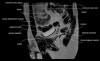

엉덩이 관절(고관절)의 MRI 단면 영상

- Checklist

1) Femur : Osteonecrosis, Fracture or Edema

2) Cartilage surface : Fissure, Fraying, Thinning or Defect

3) Joint recess : Chondral debris or Corpora aliena

4) Labrum : Tear, Detachment, Fraying or Degeneration

5) Acetabulum : Shallow contour?

6) Muscle and tendon : Tear or Strain

7) Trochanteric or Iliopsoas bursitis?

8) Check the symphysis pubis, superior/inferior pubic rami, ilium, sacroiliac joint and sacrum on large FOV coronal images